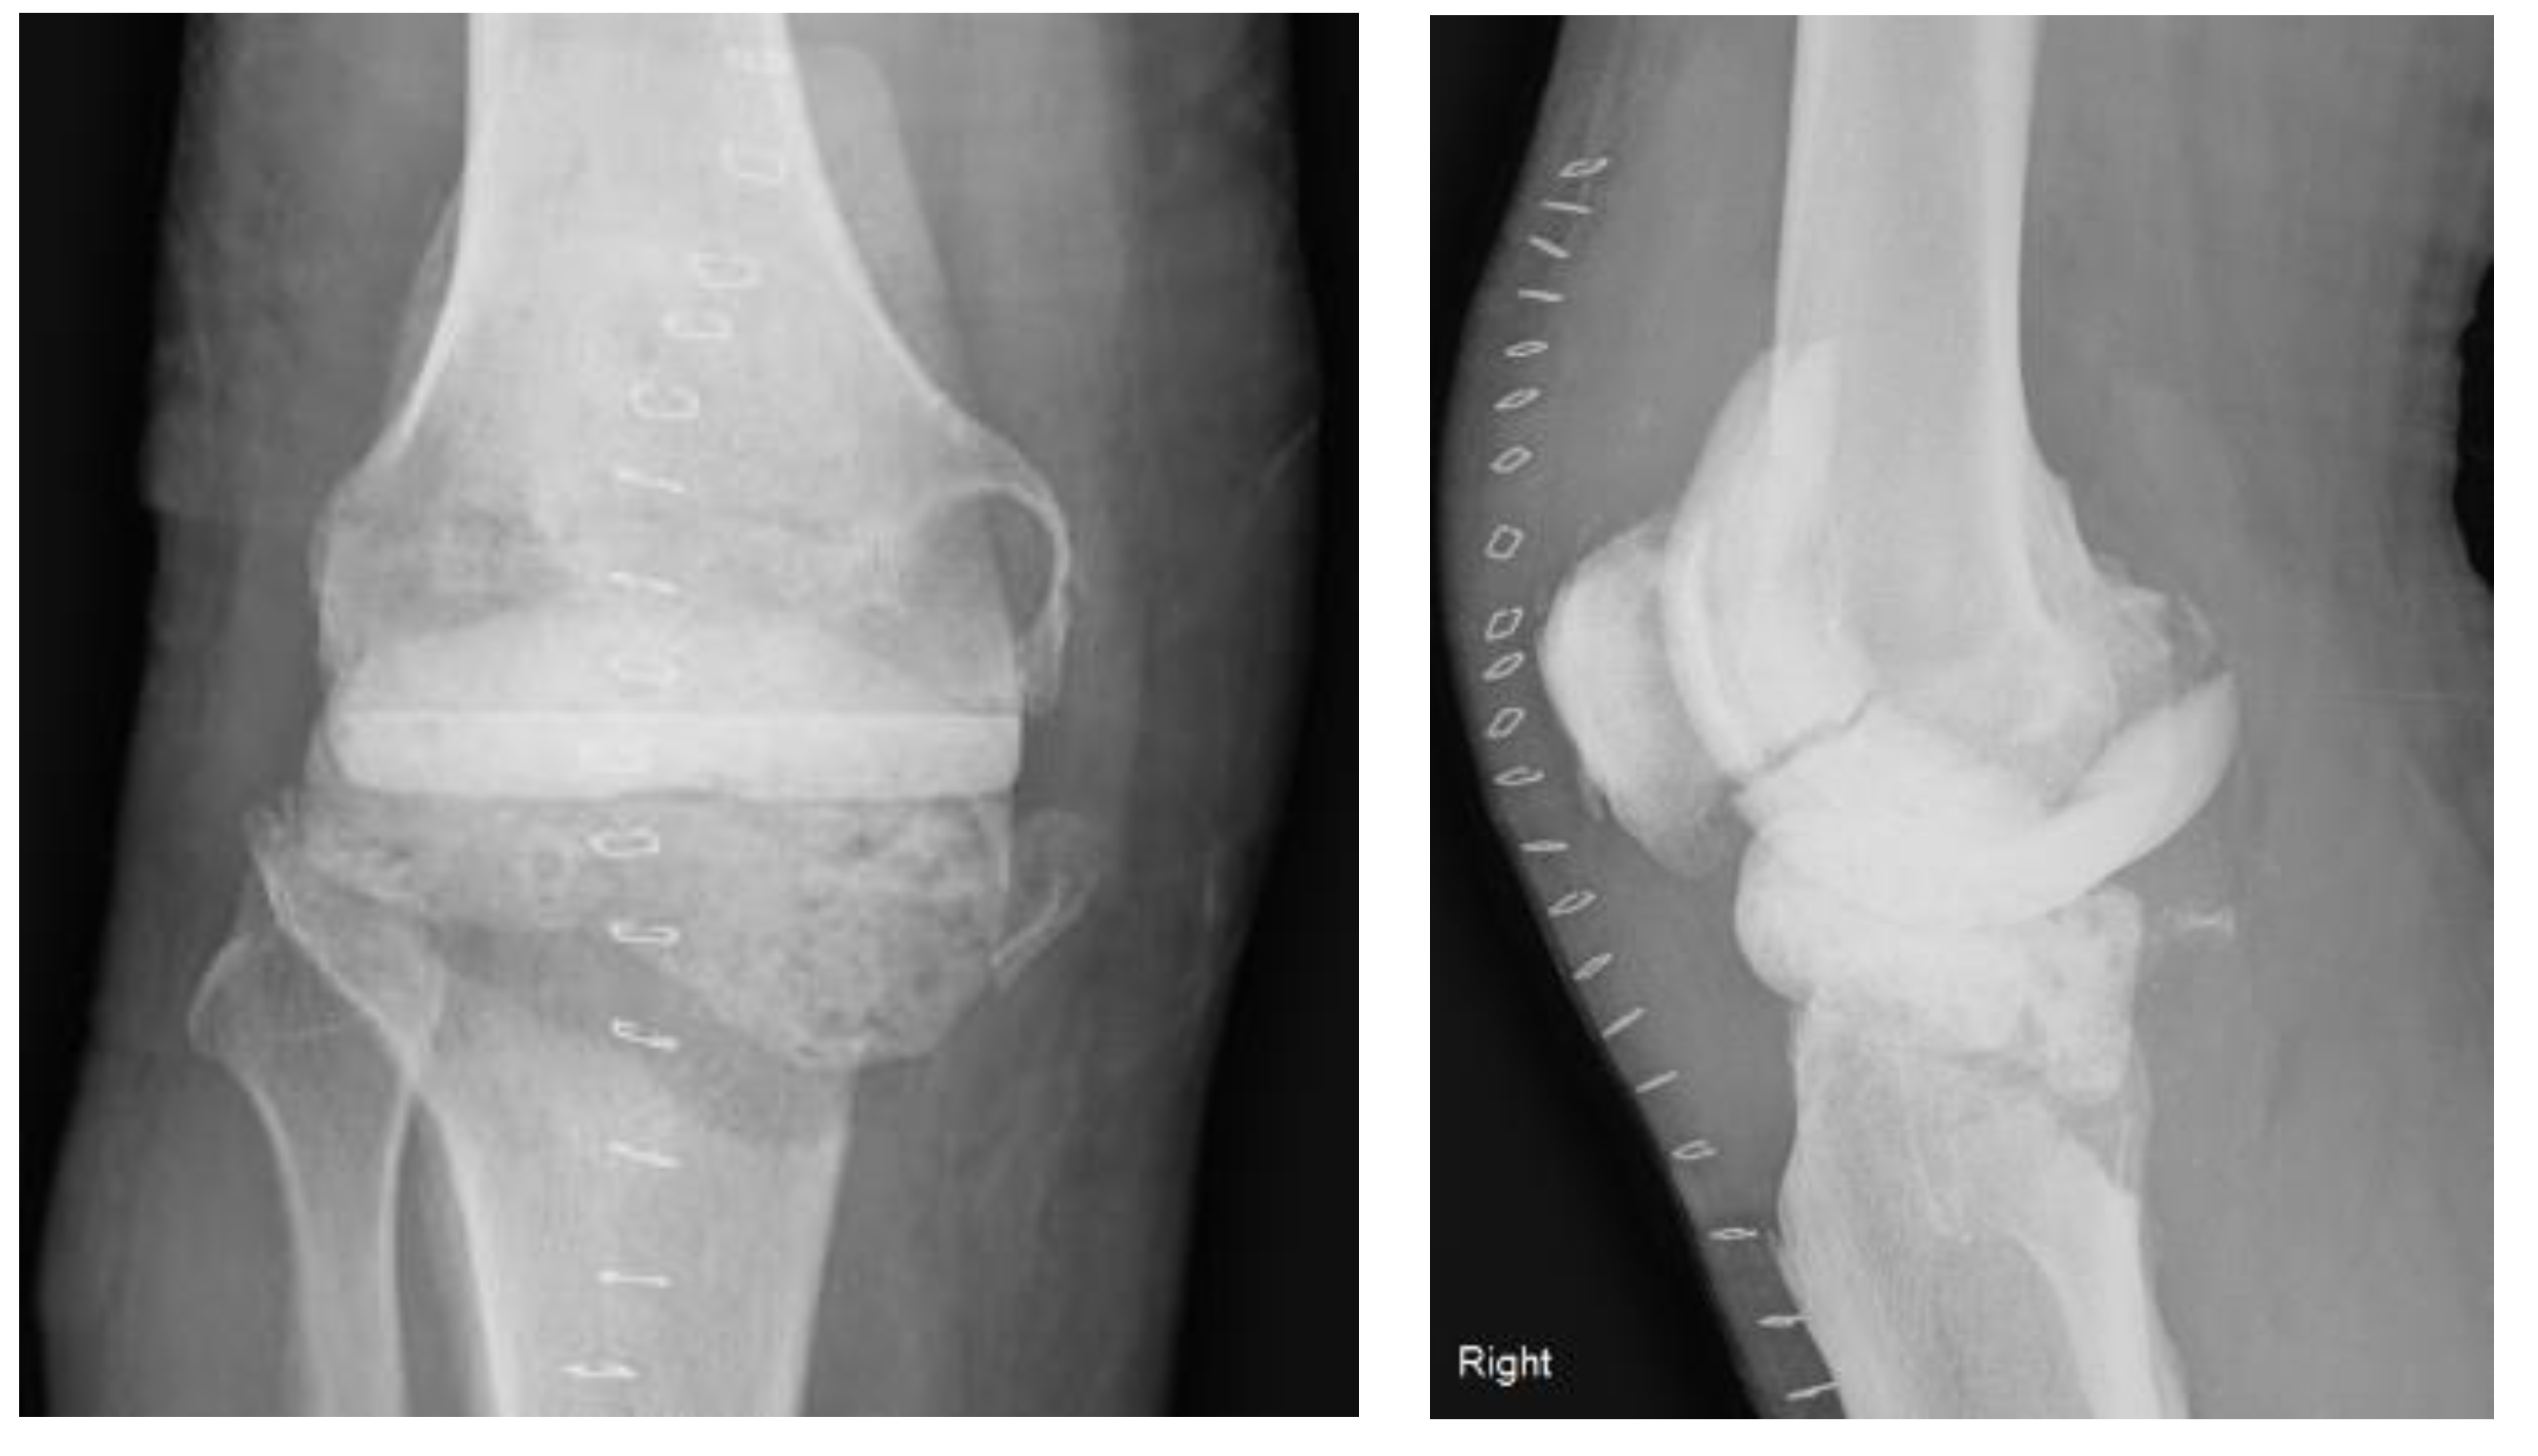

2. Case Description